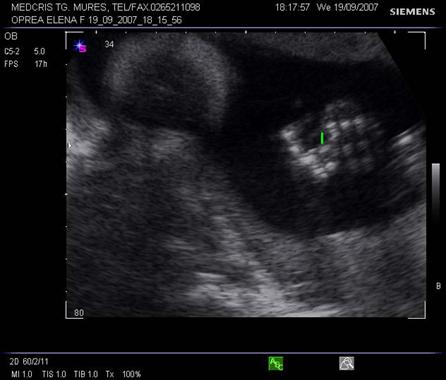

Planul V - trece prin partea bazala a mezencefalului si emisferele cerebrale. Pedunculii cerebrali formeaza aspectul de fluture, intre acestia apare fosa interpedunculara.

Fig. nr. 153. Planul V de sectiune transversala